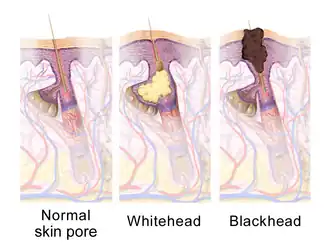

Sebaceous glands are involved in skin problems such as acne and keratosis pilaris. In the skin pores, sebum and keratin can create a hyperkeratotic plug called a comedo.

Acne is a common occurrence, particularly during puberty in teenagers, and is thought to relate to an increased production of sebum due to hormonal factors. The increased production of sebum can lead to a blockage of the sebaceous gland duct. This can cause a comedo (commonly called a blackhead or a whitehead), which can lead to infection, particularly by the bacteria Cutibacterium acnes. This can inflame the comedones, which then change into the characteristic acne lesions. Comedones generally occur on the areas with more sebaceous glands, particularly the face, shoulders, upper chest and back. Comedones may be "black" or "white" depending on whether the entire pilosebaceous unit, or just the sebaceous duct, is blocked.[31] Sebaceous filaments—innocuous build-ups of sebum—are often mistaken for whiteheads.